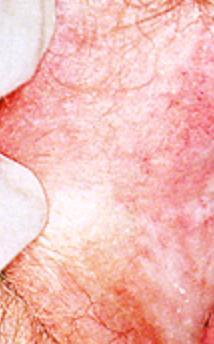

外陰白斑(硬化性苔癬型)

圖片來源:UpToDate臨牀顧問